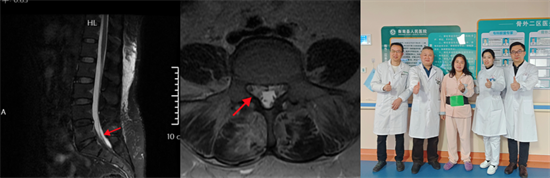

術前影像資料顯示L5/S1巨大脫出椎間盤并向近端高度游離

患者陽某某,女,50歲,因反復腰部疼痛7年加重,并右下肢疼痛麻木半月到衡南縣人民醫(yī)院就診。骨科二區(qū)主任陳軾接診了患者,門診MRI檢查發(fā)現(xiàn)陽女士為典型L5/S1巨大椎間盤脫出并壓迫神經(jīng)根,保守治療無效,建議手術治療。苗驚雷教授與縣醫(yī)院骨科二區(qū)專家團隊為陽女士量身定制了無需內(nèi)固定、創(chuàng)傷更小的UBE微創(chuàng)手術方案。術中通過兩個7mm的切口,精準摘除脫出髓核,徹底解除神經(jīng)壓迫。術后次日,陽女士下肢癥狀顯著緩解,已可自主下床活動。

術后復查MRI顯示脫出椎間盤完全摘除,

神經(jīng)松解徹底,患者術后恢復良好